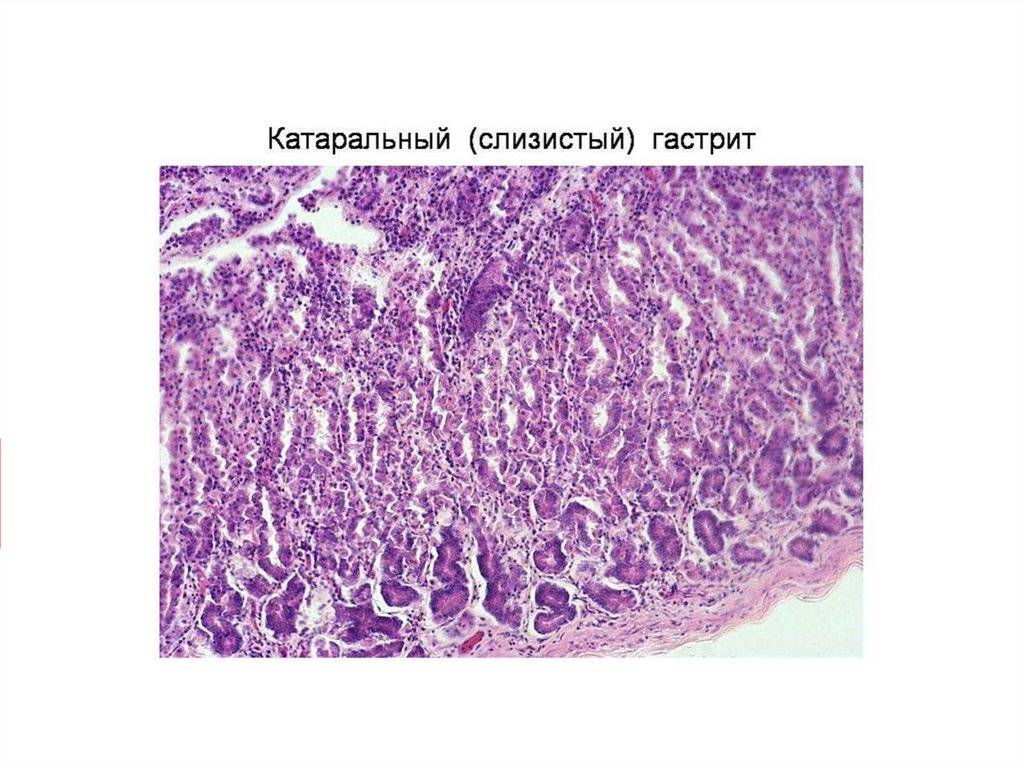

Карнификация Легкого: Микропрепараты и Диагностика

Раздел: Калейдоскоп образов